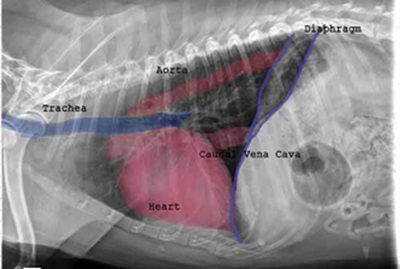

X-ray of heartRadiography (x-ray) is used to determine if the heart is enlarged (particularly the left atrium and left ventricle), if the veins from the lungs to the heart are distended, or if fluid is beginning to develop in the lungs.* X-rays also will show any enlargement of the pulmonary vein, a classic symptom of congestive heart failure (CHF).

Once a mitral valve murmur is detected by auscultation, annual x-rays are very useful in charting the progression of the disease. The 2009 ACVIM  "Consensus Statement" on degenerative MVD recommends baseline thoracic radiography for dogs with a new mitral valve murmur, then annually thereafter. However, if auscultation by stethoscope indicates that a murmur has remained mild -- Grade 1 or 2 -- and has not progressed in loudness since the murmur was first detected, a set of follow-up x-rays the next year usually is not necessary.

• Using radiography to diagnose heart enlargement

Mild to moderate heart enlargement indicates mild to moderate progression of mitral regurgitation (MR), with the heart compensating for the effects of mitral regurgitation by enlarging. Usually the dog displays no outward signs or symptoms of MVD when moderate to severe heart enlargement develops, until the dog reaches the stage of heart failure.

Cardiologists use x-rays to evaluate the size and shape of the heart in order to assess the severity of MVD. The Vertebral Heart Size or Scale or Sum (VHS) is an objective means of measuring heart size. Cavaliers with episodic falling on YouTubeAs the x-ray image above shows, using calipers, they measure the length (from the apex to the bottom of the left mainstem)  and width (at its widest point perpendicular to the lemgth measurement) of the heart on a lateral x-ray and compare those dimensions to the number of veterbrae from T4 to T12, to calculate the VHS value. Since the dog's own vertebrae are used for comparison, each VHS value is normalized to the dog's overall body size.  Measuring Vertibral Heart ScoreSee this YouTube video for details. A diagram showing how the VHS is calculated is here. This is called the Buchanan VHS method, devised by Dr. James W. Buchanan, a pioneer in the research of MVD in cavaliers, in 1995. See his 1995 article.

The VHS is not intended to diagnose CHF. It's purpose is to enable veterinarians to more accurately determine enlargement of the heart (called cardiomegaly or dilation) and the progression at which the enlargement is occurring, which usually is due to MVD. However, since MVD normally initially causes only the left atrium (LA) to enlarge, the VHS method is not precise enough to measure only the size of the LA. See for example, the x-ray at left, which shows that the VHS measurements entirely miss the bulbous enlarged LA in the upper right corner of the heart. (Image from Hezzell, 2018.)

The VHS method is most effective when it is used to compare two x-rays of the same dog's heart, taken over time, to see if the later x-ray's VHS value is higher than the earlier one, thus indicating that an enlargement of the heart has occurred. Therefore, once an MVD murmur is first detected, it is advisable to obtain an initial set of chest x-rays (called a "baseline" set) for comparison with subsequent x-rays once progression of the MVD is suspected.